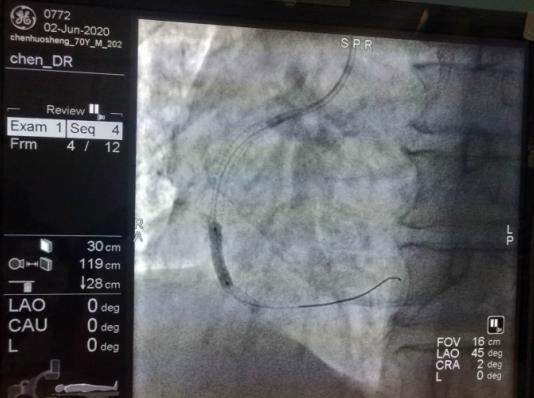

5月26日21时,一名70岁的男性患者,因突发胸痛3小时以“胸痛原因待查”,心电图提示:窦性心律,V1-V5导联ST段上斜型抬高,入科后立即予心电监护,监测生命体征。凌晨1点30分接危急值提示:肌钙蛋白I:1 .12ng/ml,患者既往有前降支和回旋支各植入一枚支架,右冠植入两枚支架病史。陈洪主任结合患者病情决定行冠状动脉造影术,经患者和家属同意后,5月29日在陈洪主任及余波主治医生为行冠状动脉造影术,术中顺利,造影结果提示:右冠中段原支架内狭窄80%。陈洪主任看到造影结果后,建议在右冠支架内病变处行药物球囊扩张术,经患者和家属同意后,于6月2日行药物球囊扩张术,术中快速将药物球囊放入到血管狭窄处,高压将药物球囊扩张,保留1分钟,药物释放后充分涂匀在血管壁上防止再次狭窄,术中顺利,术后效果良好,避免了患者再次放入支架的风险。